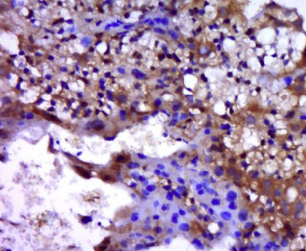

多聚甲醛固定,石蜡包埋(小鼠胎盘组织);用柠檬酸钠缓冲液(pH6.0)煮沸15min后获得抗原;用3%过氧化氢阻断内源过氧化物酶20分钟;阻断缓冲液(正常山羊血清)37℃30min;用β细胞培养液进行抗体孵育nin)未结合的多克隆抗体在1:400下在4°C下过夜,然后结合二级20分钟,DAB染色。